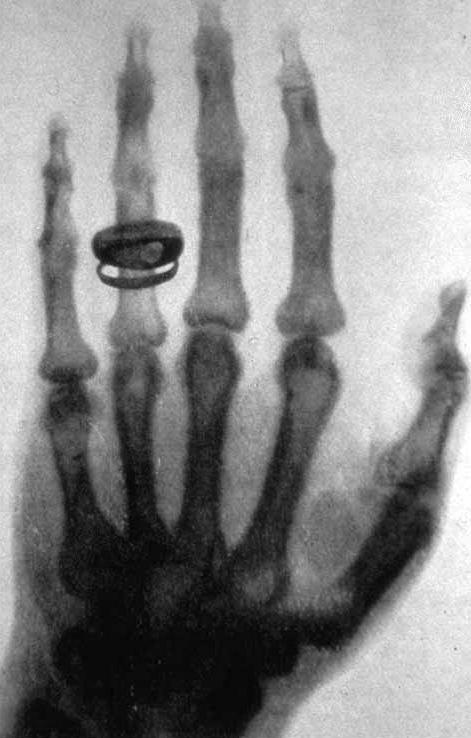

X-ray_by_Wilhelm_Röntgen_of_Albert_von_Kölliker's_hand_-_18960123-02.jpgKiedyś stosowany dużo szerzej (np. na bilansach dzieci i badaniach okresowych w pracy), dziś tylko przy wskazaniach. Na zdjęciu jedno z pierwszych zdjęć w historii, ręka Alberta von Köllikera, szwajcarskiego lekarza, który uczestniczył w demonstracji techniki. Zdjęcie często podpisuje się że to ręka Anny, żony Roentgena - takie zdjęcie też jest, ale to jest zdecydowanie ładniejsze.

Zasada działania: ustawiamy w jednej linii lampę RTG, część pacjenta do zobrazowania, i matrycę (dziś cyfrową, dekadę temu jeszcze zdarzały się klisze). Tkanki pochłaniają promieniowanie rentgenowskie, więc mniej go trafia na matrycę. Współczynnik absorpcji zależy od składu atomowego i gęstości tkanki: im więcej cięższych atomów (np. wapnia w kościach) i większa gęstość, tym jest większy. Otrzymujemy obraz w negatywie, więc im większa była absorpcja promieniowania, tym jaśniej na obrazie.

Co widzimy: sumę absorpcji “na przestrzał”. Ładnie widać oczywiście złamania i przemieszczenia kości, osteoporozę (jako kawałek kości o gąbczastej strukturze), ale też guzy w płucach (obszary o wyższej absorpcji), np. w przebiegu gruźlicy. W mammografii (tak, to zwykły RTG) widać też zmiany w piersiach.

Ograniczenia i zagrożenia: po pierwsze promieniowanie. Teraz dawki są dużo niższe, ale i tak unika się robienia prześwietlenia bez wskazań. Promieniowanie jest bardzo szkodliwe dla jajników i jąder, a także dla płodu, więc tam unikamy go szczególnie, a jak musimy to zasłaniamy płaszczami z ołowiu. Po drugie widzimy obraz 2D - nie wiemy gdzie dokładnie ulokowana jest zmiana i często potrzeba dalszej diagnostyki.

Ciekawostki: czasem podaje się kontrast - związki jodu lub baru, które mają wysokie współczynniki absorpcji i lepiej uwidaczniają przewód pokarmowy, krwionośny, albo nawet obrazują pracę nerek. Stosuje się też obrazowanie śródoperacyjne (tzw. ramię C), gdzie lekarz ma podgląd na żywo, np. jak wprowadza elektrody rozrusznika. Lampą RTG jest przeważnie działo elektronowe - identyczne jak w telewizorze kineskopowym. Telewizory radzieckie, jak sławny Rubin, “świeciły” dosyć mocno, i dobrze że mama kazała siadać daleko.